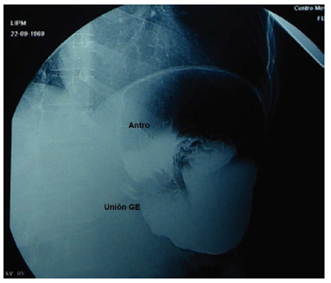

Masculino de 49 años de edad sin enfermedades crónicas ni cirugías previas y con antecedentes de pirosis y reflujo de larga evolución, se presenta a urgencias con melena de 4 días, ardor epigástrico, diaforesis, palidez de tegumentos, astenia y adinamia. Por endoscopia se diagnóstica HPE con VG y una ulcera gástrica de 1 cm en fundus con vaso visible y estigmas de sangrado, manejada con adrenalina. Es manejado en un inicio medicamente con sonda nasogástrica e inhibidores de la bomba de protones. Requiere transfusión de 2 paquetes globulares. Se realiza serie esófagogastroduodenal (SEGD) en la que se observa más de la mitad del estómago dentro del tórax con vólvulo organoaxial (fig. 1). Es intervenido en forma electiva realizando destorsión y reducción gástrica, plastia hiatal con malla de politetrafluoretileno (PTFE) de 10 × 7 cm y FN por laparoscopia con 5 puertos, 3 de 5 mm y 2 de 10 mm. Se disecó y resecó completamente el saco herniario cuidando de no dañar las estructuras adyacentes como la pleura y los nervios vagos, se seccionaron los vasos cortos, se cerró el hiato con puntos de poliéster y se reforzó con una malla de PTFE fijada con sutura. No se realizó gastropexia. El tiempo quirúrgico fue de 120 min, sangrado transoperatorio de 10 cc, sin complicaciones y 2 días de estancia intrahospitalaria (figs. 2 y 3). Tres meses después de la cirugía se realizan panendoscopia y manometría reportadas normales con funduplicatura competente y esfínter esofágico inferior con longitud 5 cm y presión 12.62 cm y peristalsis efectiva en 100% de las degluciones. A los 18 meses se realiza nuevamente panendoscopia que reporta funduplicatura funcional sin esofagitis. A los 5 años de la cirugía la evolución del paciente es satisfactoria con curso asintomático.

Figura 2 Transoperatoria del caso 1 1ue muestra vólvulo gástrico (VG) mesentéricoaxial intratoráccico en reducción.